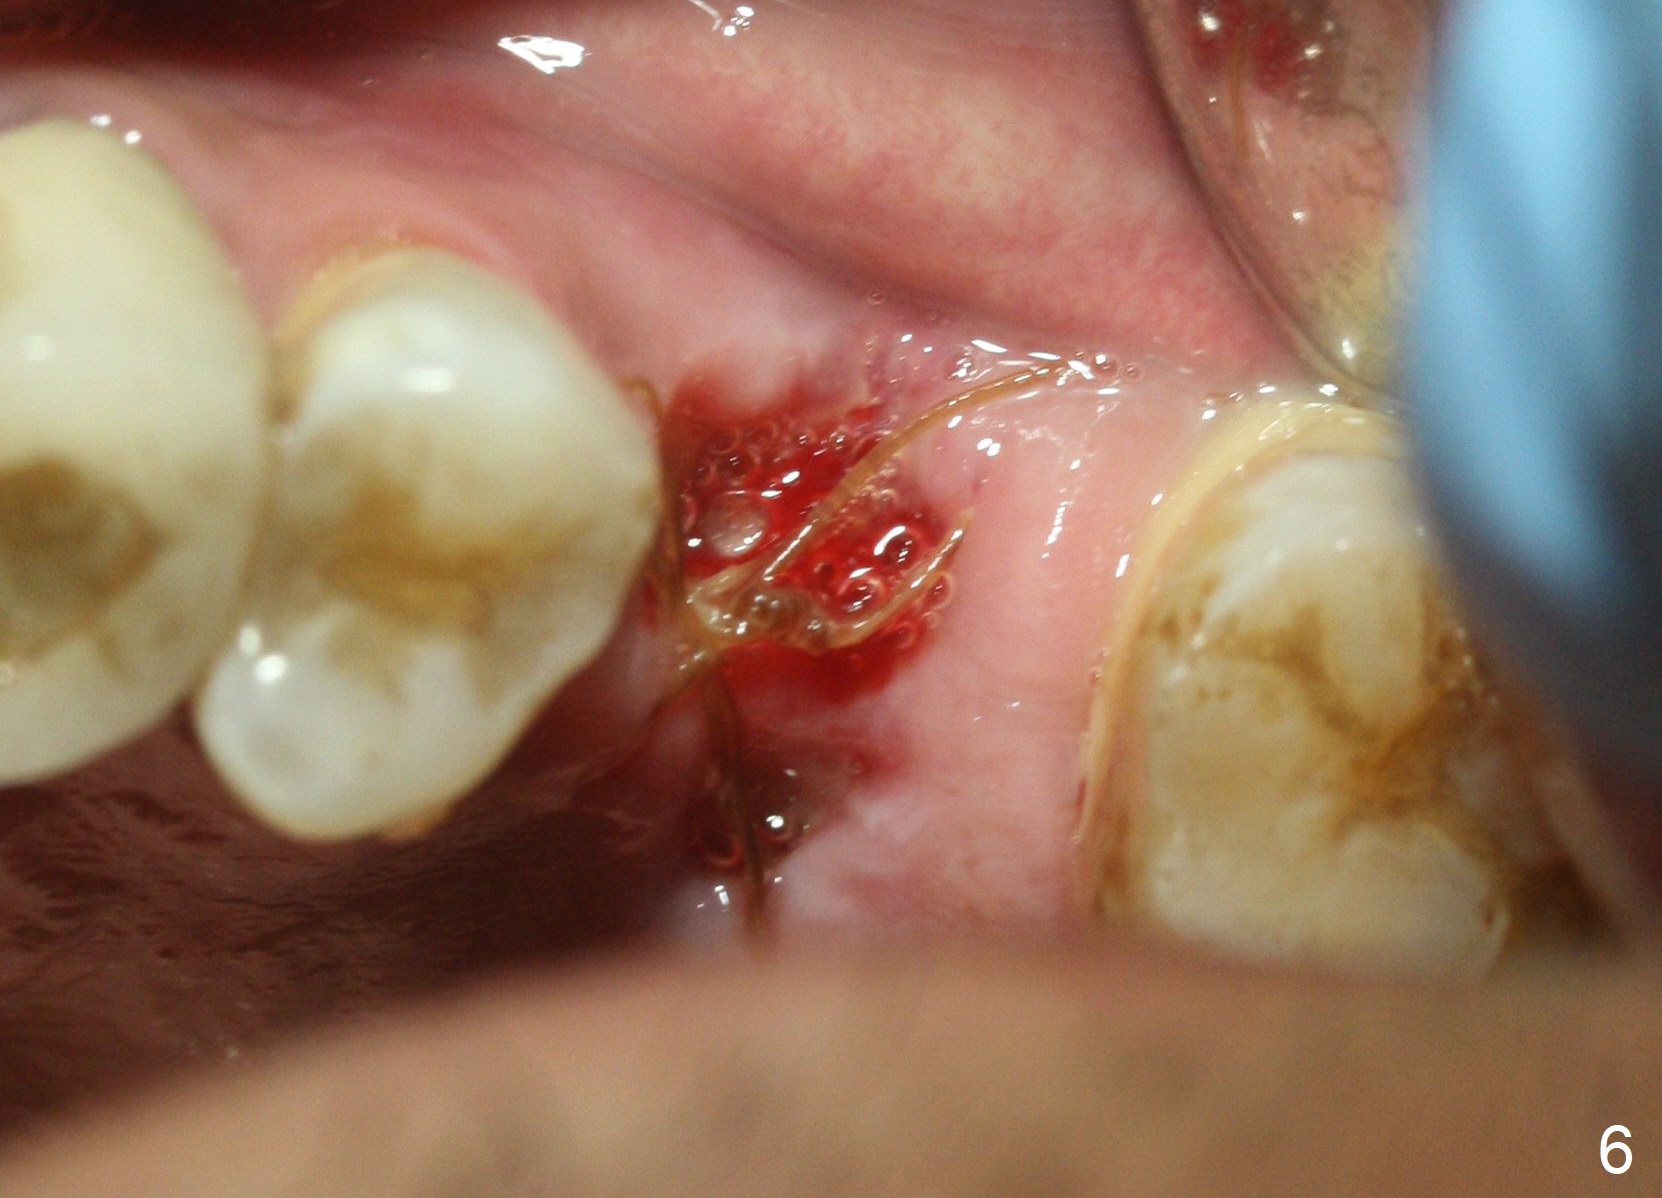

When the tooth #14 is extracted, the buccal plate is lost, while the apex of the palatal socket is perforated.  The palatal slope of the septum appears to be a suitable site for osteotomy, but the depth seems to be 2 mm.  After sequential osteotomy until 5.3 mm with drills, a 5.9 mm SM tap obtains stability (Fig.2).  A 5.9x8 mmm implant is placed with barely sufficient stability after 1 piece of PRF membrane and VeraGraft (Fig.2-4).  The implant rotates and dislodges when an abutment is being placed.  Neither do 6-8x17 mm Tatum taps achieve primary stability.  Socket preservation is performed, followed by periodontal dressing (Fig.5).  Primary stability might have been obtained if a smaller IBS implant with fins were placed in the palatal socket.  The periodontal dressing has dislodged 1 week postop; the socket appears healing (Fig.6,7).  Bone graft seems to be minimal or bone density of the graft is low (Fig.8).  The socket heals with a wide ridge 2 months post socket preservation, but the tooth #15 seems to be buccal (Fig.9) and mesial (Fig.10) shift.  After use of Magic Split and Expanders (until 3.8 mm for 13 mm), try 5 mm dummy implant (Fig.11).  If 6 mm one fails to achieve stability substantially, switch to 7 mm Tatum tapered tap provided there is enough mesiodistal space (use 8 mm implant positioner to gauze the space beforehand (preop)).  Consider using Vanilla (not Vera) Graft to fill in the gap between implant and osteotomy.  When primary stability is obtained, place a nonfunctional provisional to prevent further shifting (Fig.11 white outline).  After osteointegration, use the provisional (reline and separator) to distalize the tooth #15.